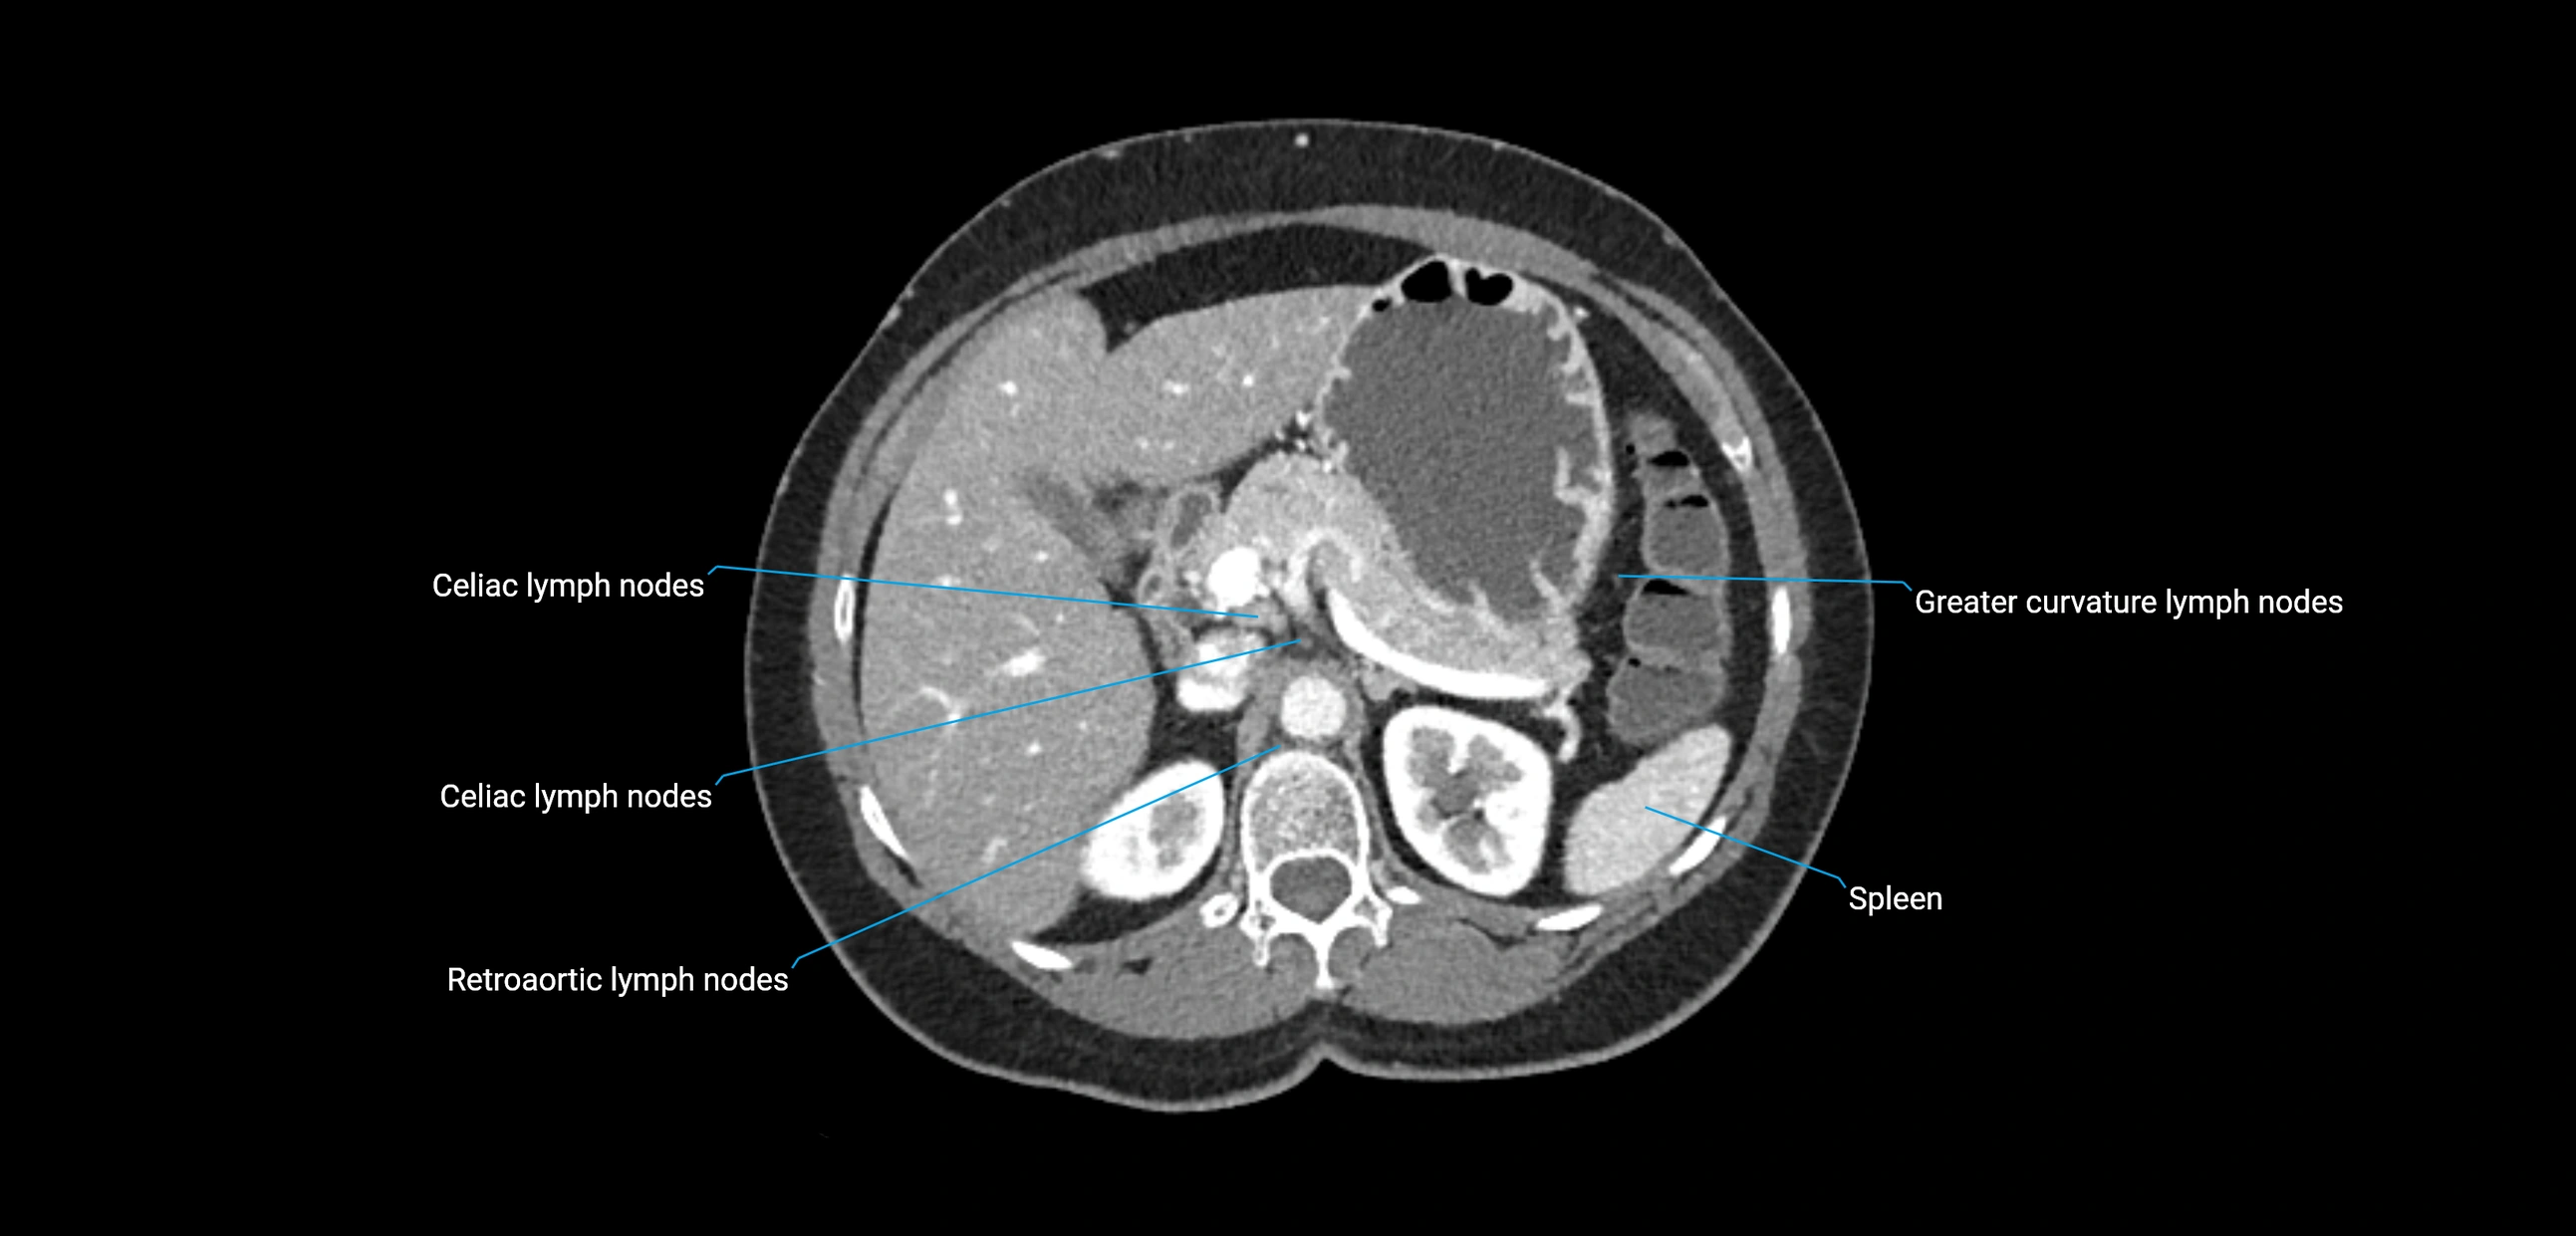

CT Appearance

CT Pre-Contrast:

• Nodes appear as soft-tissue density nodules adjacent to the aorta and IVC

• Calcification may be seen in chronic infections (e.g., tuberculosis)

CT Post-Contrast:

• Normal nodes enhance homogeneously

• Malignant nodes may show heterogeneous enhancement, central necrosis, or conglomerate formation

• Size >1 cm short axis is suspicious, though morphology and distribution are equally important